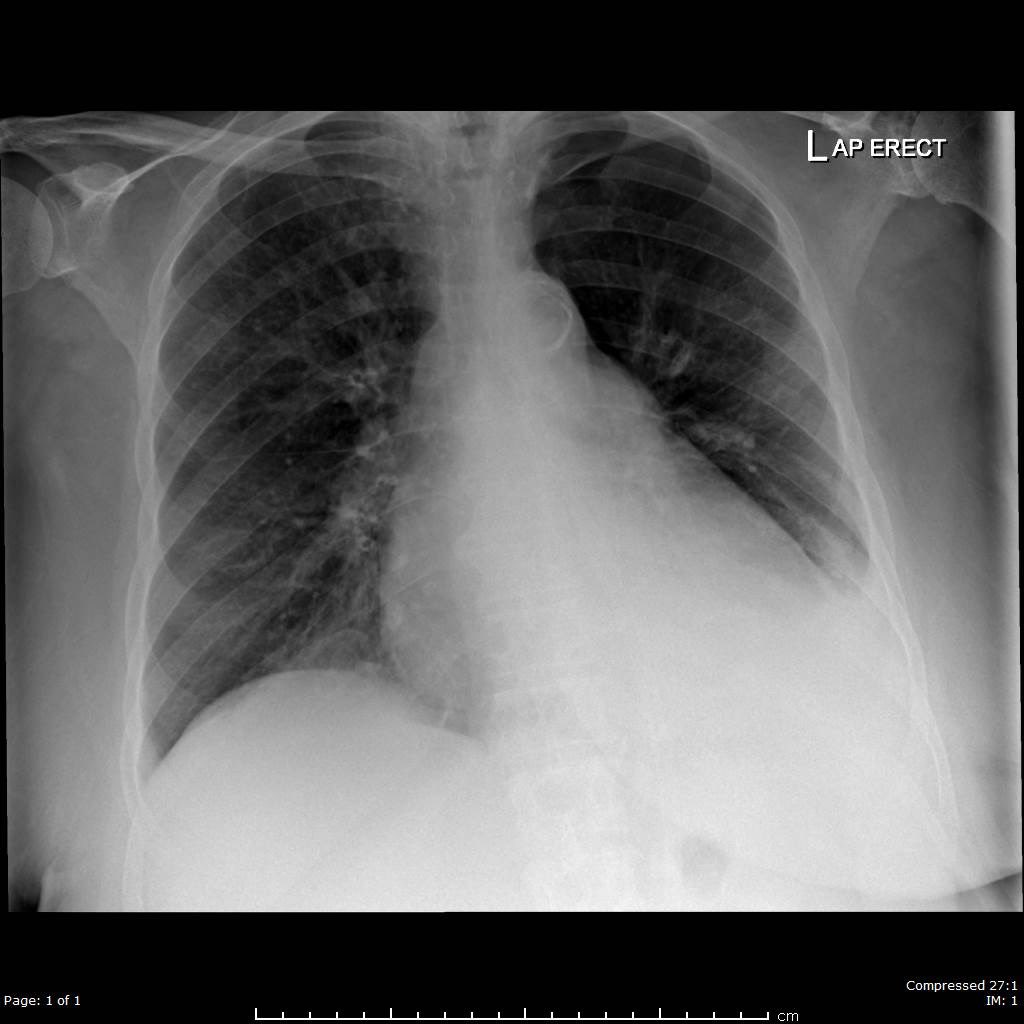

The latest CXR now is shown here:

The latest CXR now is shown here:

4/10 Pt was at risk of further deterioration with decompensated type 2 respiratory failure and may need further NIV. Our concern was whether she had developed a pneumothorax even with a ‘normal’ looking chest x ray.

Note: In hindsight, when we looked at her #CXR at deterioration again, maybe you could make out the slight increase in translucency on the left upper region to suggest a #pneumothorax. #RespisBest #RespEd